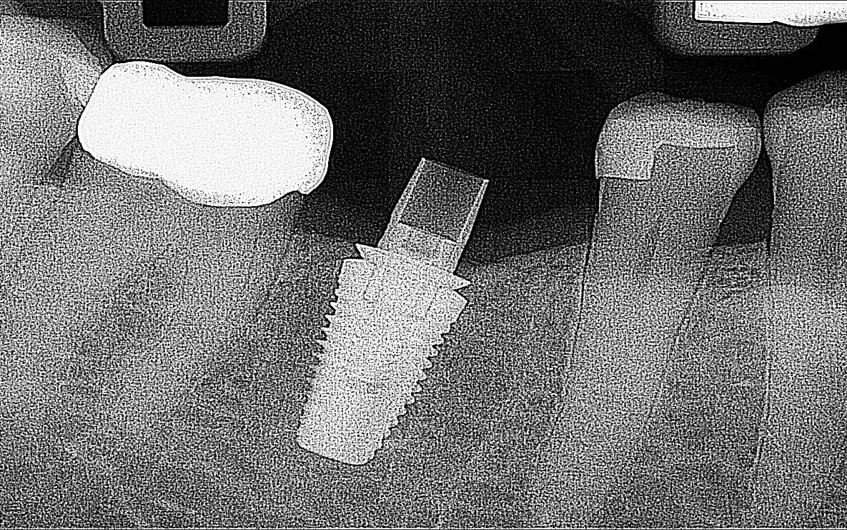

A dental Implant is a titanium “root” that integrates directly with the surrounding bone and replaces the function of the natural tooth. Neoss Implants are made using the best quality medical grade titanium, which is well known for its proven biocompatibility, and have a treated surface to facilitate bone integration.